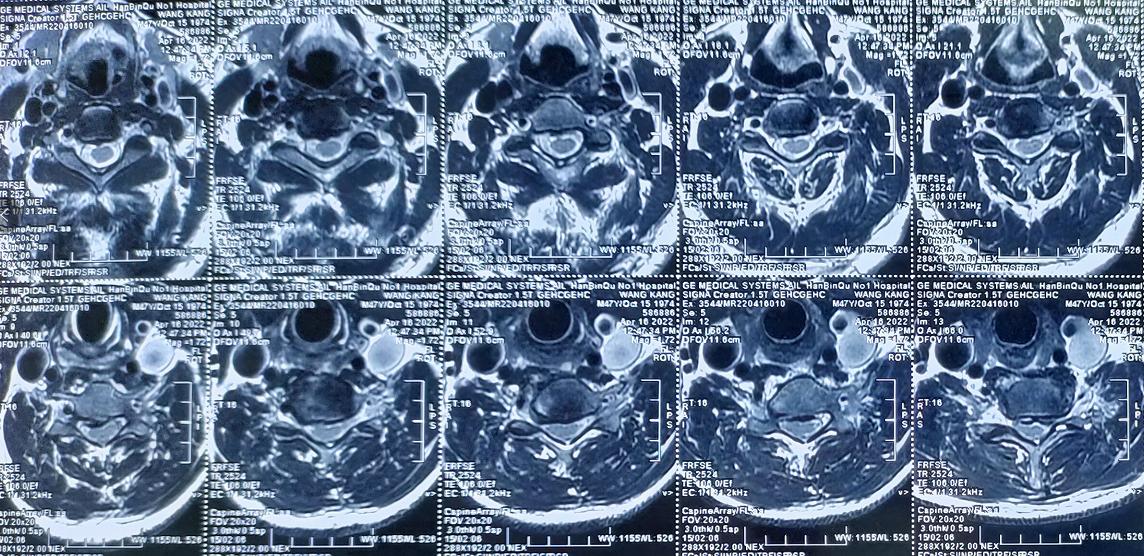

廖博主任接诊后,结合王先生的影像学资料、症状表现以及其他检查结果,最终确诊他为“平山病”。由于患者颈椎严重反曲,且脊髓腹侧受到压迫,廖博主任建议尽快进行手术治疗。

术前影像学资料: